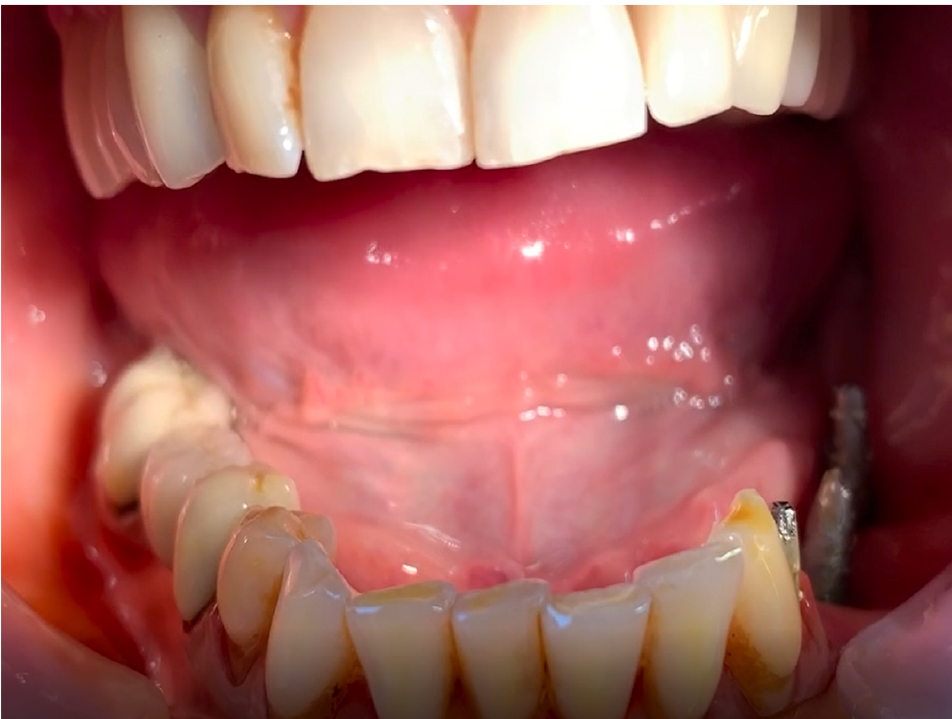

Средний возраст пациент составил (34,4 ± 4,2) года. На этапе ортопедического протезирования больным было изготовлено 108 коронок, из них металлокерамических – 87 (80,6 %), керамических безметалловых – 9 (8,3 %), цельнолитых – 12 (11,1 %). Все пациенты согласно методам подготовки к ортопедическому лечению были рандомизированы на 3 группы. Пациентам первой группы (32 человека) одним из методов подготовки была выполнена гингиворетракция десны, во второй группе (31 человек) – метод гингивэктомии и в третьей группе – гингивопластика зубодесневого комплекса (32 человека) (рис. 1).

Клинический успех лечения оценивали путем соотношения шансов, который выражается соотношением повышенного риска и нормальной восприимчивости. Для определения факторов риска, так называемых факторов-предикторов, которые могут спровоцировать развитие воспаление зубодесневого комплекса, применяли следующие индексы – приблизительный индекс зубного налета – API, индекс сосочковой кровоточивости (PBI), пародонтальный индекс нуждаемости в лечении (CPITN), индекс рецессии десны по Miller. Алгоритм диагностики и ведения пациентов заключался в следующем. Проводилось комплексное поэтапное обследование. На первом этапе собран анамнез жизни и заболеваний пациента с выявлением существующих рисков (приобретенный или генетический уровень). На втором этапе произведен сбор клинических данных до начала проведения подготовки к ортопедическому лечению: оценка пародонтального статуса, уровня рецессии десны, вовлечение фуркации, активность карманов, подвижность зубов, оценка воспаления десны с проведением гигиенических индексов (рис. 2).

На первостепенном уровне проведена запись клинических данных («золотой стандарт»). Затем выполнена визуальная диагностика с помощью стоматологического зеркала, особо внимание уделяли скоплению зубного налета, выявление рецессии десны (рис. 3). Клинический осмотр на каждом этапе включал измерение глубины зондирования кармана и потери прикрепления (рис. 4). Сила зондирования составляла 0,20 Н, что соответствует 25 г.